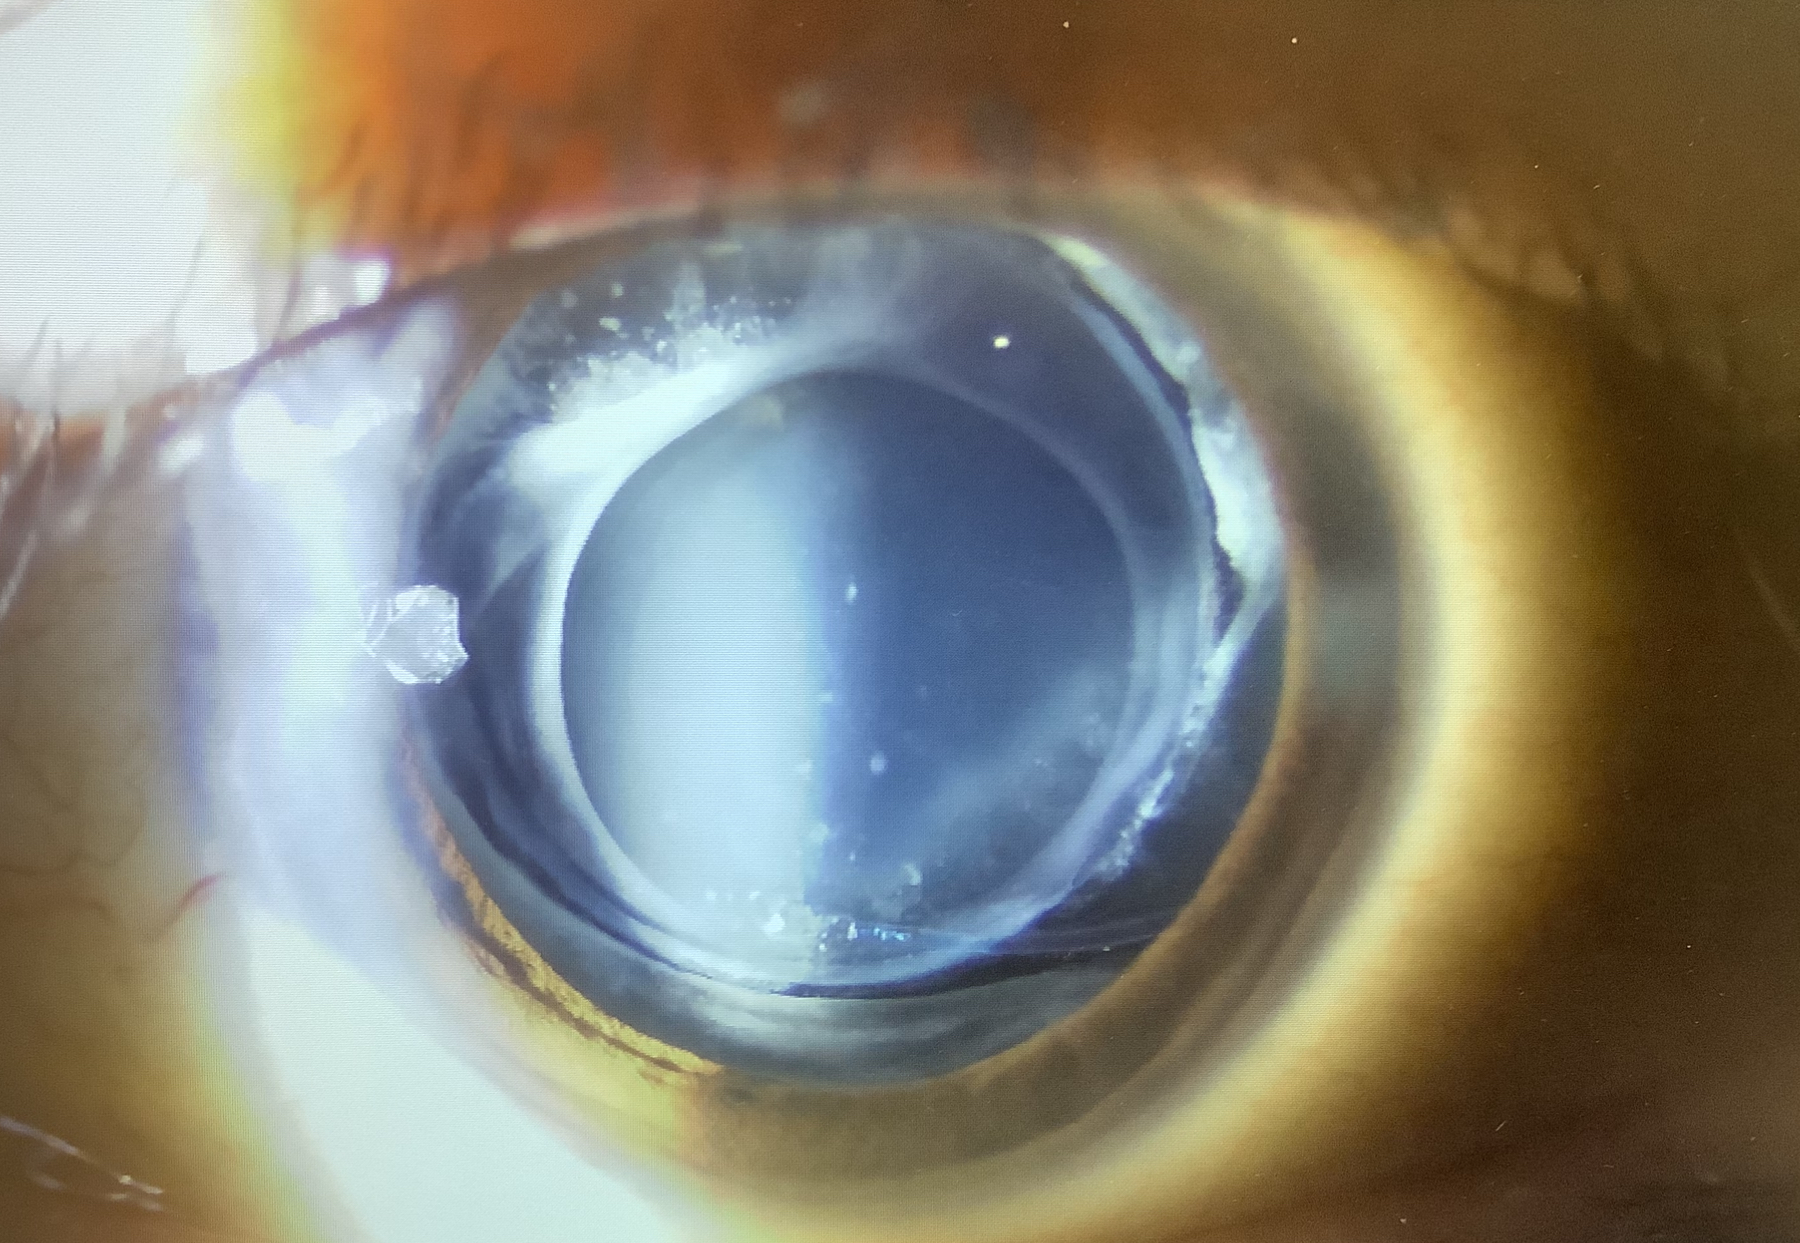

外来では僕が昭和大学藤が丘病院に在籍していた時の患者さまが訪れて来てくださいました。右眼は2008年に谷口教授が、左眼は2013年に僕が白内障の手術をした方で、今回は後発白内障で見えにくくなり、YAGレーザーを行わせていただきました。